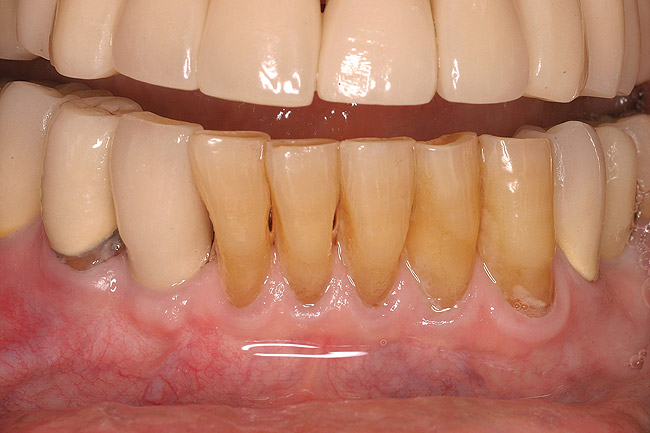

Patients present for tooth extraction for various reasons (eg, caries, periodontal disease).1 The dental literature describes loss of bone volume after dental extractions of up to 50% within 6 months.2-4 The effect of bone loss is magnified when multiple teeth are extracted in the same area.5 Bone resorption will result in a loss of socket width in an apical and lingual direction. Socket collapse can prevent or significantly inhibit the placement of dental implants in ideal, prosthetically driven positions.6 Severe loss of alveolar volume may necessitate ridge augmentation by block grafting and other extensive surgical procedures if dental implants are to be placed for the support of a prosthesis.7

Thirty patients were selected on the basis of need for dental extractions with bone preservation and/or augmentation in the socket before the placement of a dental implant. These patients were cleared medically for oral surgical procedures. Preoperative clinical photographs and periapical radiographs were taken. After administration of local anesthesia, full-thickness labial and lingual/palatal flaps were elevated. Minimal soft-tissue manipulation was performed to allow visualization of the entire alveolar crests and debridement of fenestrations and/or dehiscence defects, if present. Elevation of each tooth or retained roots was performed, using periotomes, luxatomes, proximators, root forceps, and any other instruments and procedures as required to extract the tooth with minimal trauma (Figure 1). After extraction and thorough debridement of the socket by mechanical means, clinical photographs were taken. The sites then were grafted with a resorbable β-TCP of small particle size, 150 µm to 500 µm (Cerasorb) (Figure 2). This material has been used and reported in the literature for almost 30 years as a viable bone graft in orthopedic and other surgical specialties. In this study, the granules of β-TCP were mixed thoroughly with blood from the surgical sites and the sockets filled to ideal contours faciolingually and apicocoronally. The grafts and adjacent 3 mm of alveolar bone then were covered with resorbable collagen barriers (BioMend®, www.zimmerdental.com) (Figure 3). The flaps were repositioned and the areas closed with an appropriate number and type of sutures. No attempts were made to obtain primary closure over the exposed barriers. Postoperative radiographs and clinical photographs were taken. Subsequently, sutures were removed at 1 to 2 weeks.

Figure 1  Occlusal view after extraction of tooth No. 27 using Piezosurgery<sup>®</sup> (Piezosurgery Inc, www.piezosurgery.com) and thin-bladed elevators.

Figure 1

Figure 2  The extraction socket was grafted with a mixture of pure-phase β-TCP and heme from the surgical site.

Figure 2

Figure 12  A patient who had tooth No. 2 extracted using Piezosurgery, periotomes, thin-bladed elevators, and small-beaked forceps, enabling preservation of all bony peaks.

Figure 12